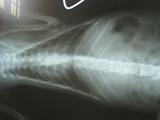

- 編號: 378

主題: 有血便和肺炎的橘白貓咪 申請者姓名: 敏大哥 花色: 申請日期: 2012-06-02 21:20:49 申請者部落格: 申請者臉書網址: 所在縣市/合作醫院: 台北市/詠欣動物醫院 治療費用: 6900元 需求人數: 8人 已結案 (2012-12-01 19:30:28) 報名人員: Huei Wen Chuang(已付款)、小舟(已付款)、阿金(已付款)、貞子(已付款)、Chao ping(已付款)、嘟嘟(已付款)、嘟嘟(已付款)、嘟嘟(已付款)、 候補人員: 小舟、小舟、 動物病情說明: 平溪張媽媽抓的貓.自TNR後,這隻貓一直精神食慾不好,呼吸有點喘.近來又有血便.就趕緊帶牠就醫.醫生說,有肺炎 便便有鞭蟲,貓咪又帶有野性.在反覆氣霧 驅蟲.食慾精神調理較正常 再帶回山上照顧.